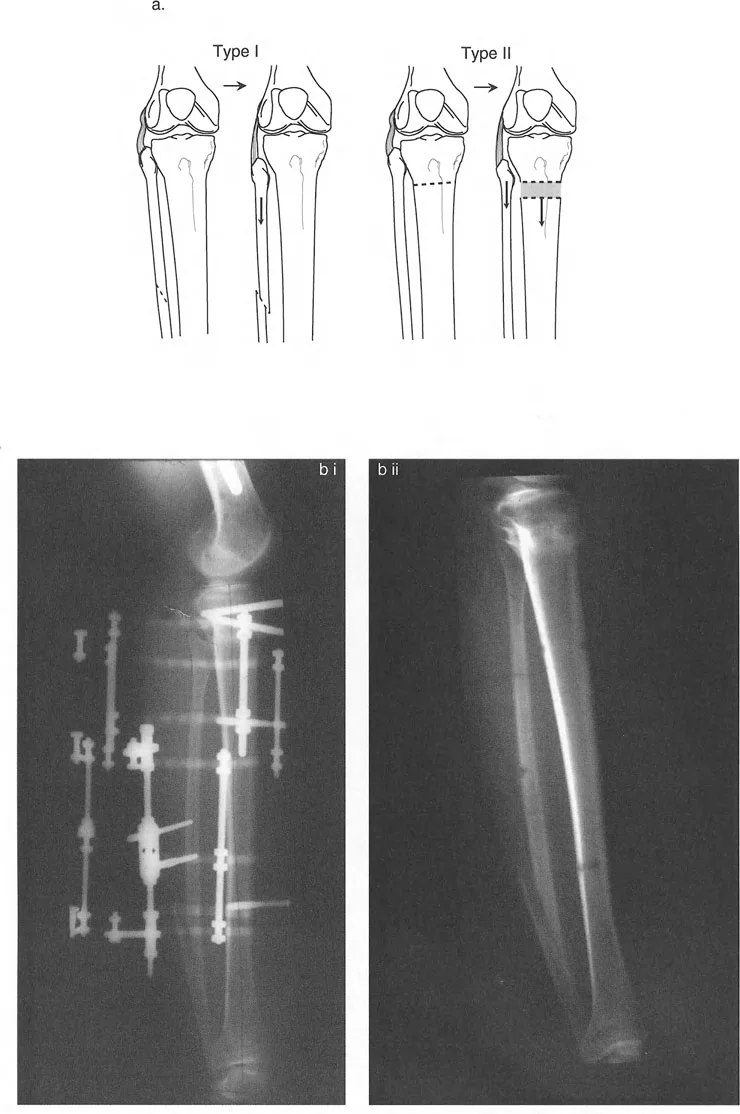

Paley Osteotomy Rules

Identifying the CORA is only half the battle. The surgeon must then decide where to make the bone cut (the osteotomy) and where to place the hinge (the Axis of Correction of Angulation, or ACA). Paley codified three fundamental osteotomy rules that dictate the biomechanical outcome of a correction.

Osteotomy Rule One Pure Angulation

Rule One: When the osteotomy and the ACA (hinge) both pass through the CORA, pure angulation occurs without any translation.

This is the most biomechanically sound and biologically favorable method of correction. Because the bone ends pivot directly around the apex of the deformity, the mechanical axis is perfectly restored, and the bone ends remain in excellent cortical contact, promoting rapid osteogenesis and healing.

Osteotomy Rule Two Angulation and Translation

Rule Two: When the ACA (hinge) passes through the CORA, but the osteotomy is performed at a different level, the correction will result in both angulation and translation of the bone ends.

Clinically, this rule is utilized when the CORA is located very close to a joint line, making a Rule One osteotomy impossible due to the lack of adequate bone stock for fixation. By making the osteotomy further down the diaphysis but keeping the hinge at the CORA, the mechanical axis is still perfectly restored. However, the surgeon must anticipate and allow for the resulting translation at the osteotomy site. Attempting to force the translated bone ends back together will result in a failure to correct the mechanical axis.

Osteotomy Rule Three Iatrogenic Translation

Rule Three: When the osteotomy and the ACA (hinge) are both placed outside the CORA, the result is a massive iatrogenic translation and a failure to correct the mechanical axis.

This rule defines what happens when deformity correction is planned poorly. If a surgeon simply cuts the bone at a convenient location and bends it without respecting the CORA, a secondary translation deformity is created. The mechanical axis will remain deviated, and the joint will continue to experience eccentric focal overloading. Rule Three is a warning of what to avoid in clinical practice.

For acute corrections of single-apex deformities, internal fixation is often preferred due to patient comfort and rapid rehabilitation.

Opening wedge or closing wedge osteotomies can be rigidly stabilized with modern locking plate technology. When the CORA is diaphyseal, an intramedullary nail is an excellent biomechanical option. However, correcting a deformity with a straight nail in a curved tube presents unique challenges. The surgeon must frequently employ blocking screws, also known as Poller screws, to intentionally narrow the medullary canal and force the nail to follow the corrected mechanical axis, preventing the bone from sliding back into deformity.

Circular External Fixation and Hexapod Systems

For complex, multi-planar deformities, multi-apical deformities, or deformities associated with significant limb length discrepancy, circular external fixation remains the gold standard.

Modern hexapod systems, such as the Taylor Spatial Frame, utilize the principles of a Stewart platform. By inputting the exact radiographic parameters, the CORA location, and the mounting parameters into a software program, the computer generates a daily schedule of strut adjustments. This allows for the gradual, simultaneous correction of angulation, translation, rotation, and length. Gradual correction also protects neurovascular structures, which can be stretched and damaged during large acute corrections.